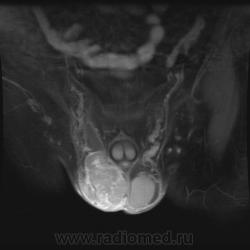

- https://radiomed.ru/sites/default/files/styles/case_slider_image/public/user/1/testis3-t2fs-ax.jpg?itok=hg7dh1HQ

- https://radiomed.ru/sites/default/files/styles/case_slider_image/public/user/1/testis4-t2fs-cor.jpg?itok=awoxfYmC

"Мужчина, 60 лет. Около 3 месяцев назад появился дискомфорт в области мошонки, увеличение правого яичка."